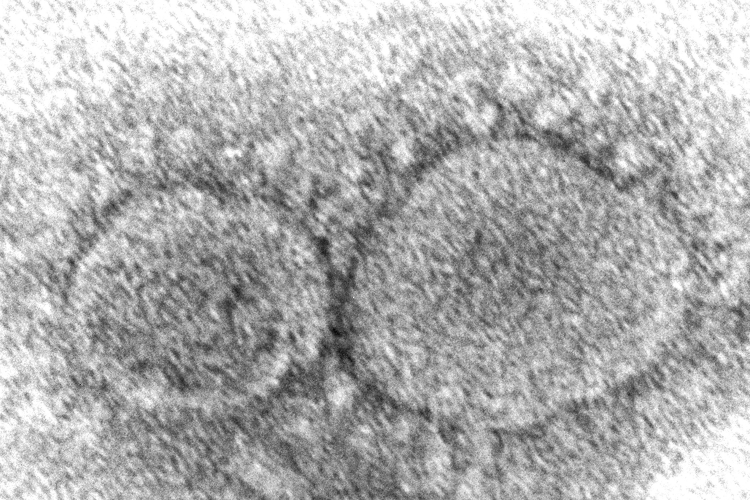

Scientists are pretty sure that #COVID_19 was a zoonotic spillover, but China is preventing any effort to conclusively know the origin by refusing to release needed data. via @ScienceBasedMed realclearscience.com/2026/03/05/the…